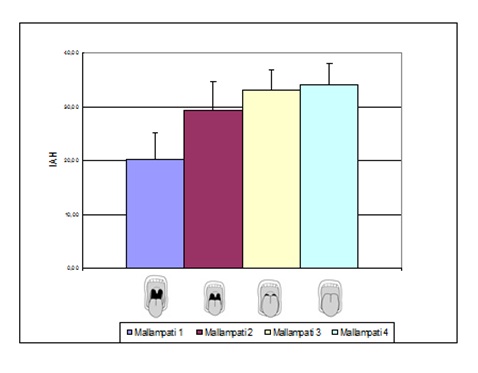

Los signos frecuentes se presentan en la Tabla 6. La figura 3, La figura 4, La figura 5 y La figura 6 describen los hallazgos de importancia en el examen de cuello y de la orofaringe, que habitualmente son escasamente destacados en la enseñanza de la semiología. La circunferencia de cuello fue de 45,9 ± 3,9cm en hombres (normal hasta 42) y 41,8 ± 3,7cm en mujeres (normal hasta 38). El espacio crico-mental se evaluó cualitativamente15. En el examen de la orofaringe, se evaluaron los grados de Mallampati16, como predictores de severidad de apneas del sueño. Los grados más altos se asociaron a IAH mayores, aunque en forma no significativa (Figura 7).

Figura 7: Grados de Mallampati y severidad de apneas del sueño (IAH). El examen de la orofaringe durante la apertura bucal y protrusión de la lengua (sin fonación) permite evaluar globalmente las estructuras anatómicas. Grado I: paladar blando, úvula, istmo de las fauces, pilares anteriores y posteriores visibles. Grado II: paladar blando, parte de la úvula e istmo de las fauces visibles. Grado III: paladar blando y sólo base de la úvula visibles. Grado IV: solamente es visible el paladar duro.